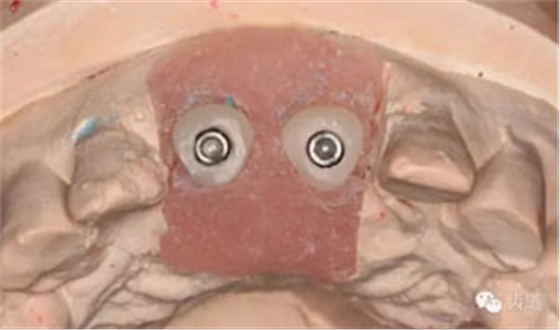

制作個(gè)性化愈合基臺(tái)(參考原牙頸部外形)

換用個(gè)性化愈合基臺(tái)(術(shù)后一周)

試戴臨時(shí)活動(dòng)義齒

半年后復(fù)診(牙齦袖口)

個(gè)性化取模樁